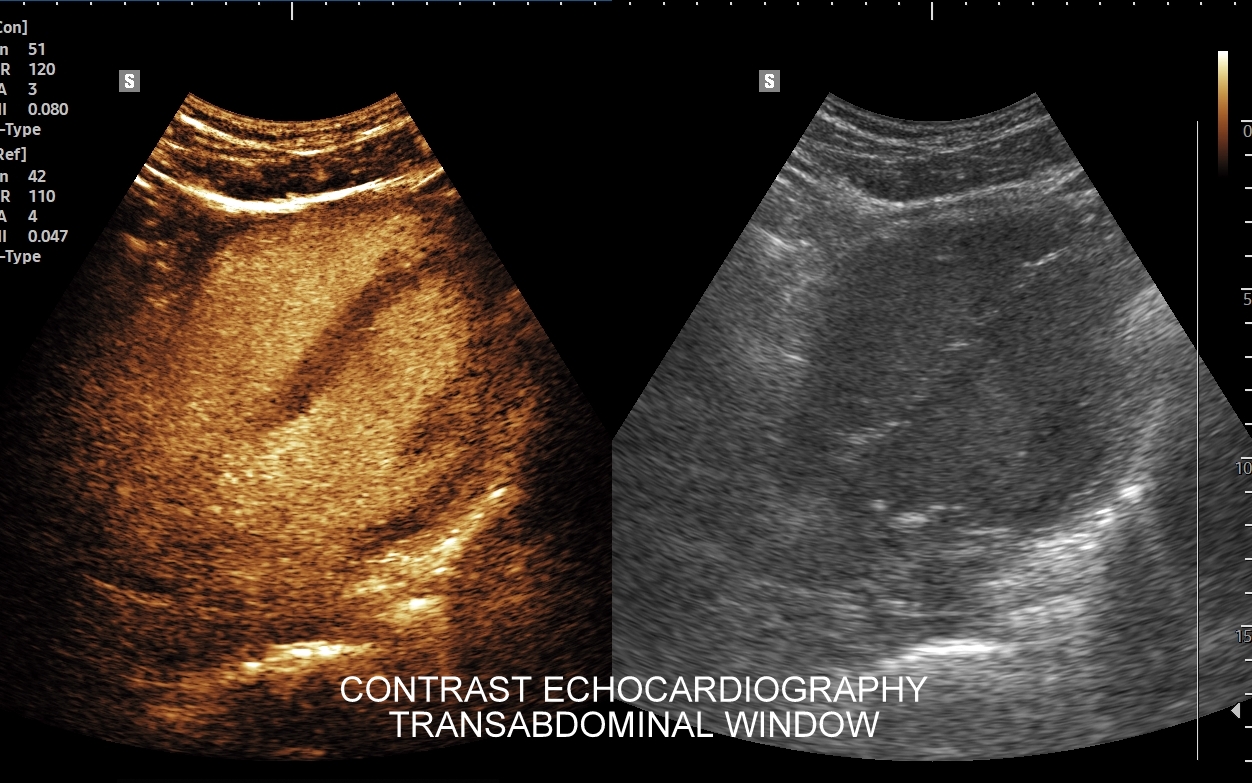

Specjalista chorób wewnętrznych z wieloletnią praktyką kardiologiczną i naczyniową. Szkolenie USG serca odbywał w Pododdziale Kardiodiagnostyki w Klinice Chirurgii Serca Akademii Medycznej we Wrocławiu. Jeden z najbardziej doświadczonych sonografistów w Polsce. Posiada ponad 25-letni staż kliniczny i szkoleniowy w Polsce oraz zagranicą (Wielka Brytania, Niemcy, Austria, Włochy). Wykonał ponad 40.000 badań USG. Wprowadził do rutynowego zastosowania w Polsce takie procedury diagnostyczne jak USG z kontrastem (CEUS) oraz multiparametryczne badania USG (MPUS). Certyfikowany lekarz Polskiego Towarzystwa Ultrasonograficznego z zakresu badań naczyniowych. Na co dzień dr Szczepański zajmuje się przeglądami zdrowia oraz specjalistyczną diagnostyką z zakresu chorób wewnętrznych i serca.